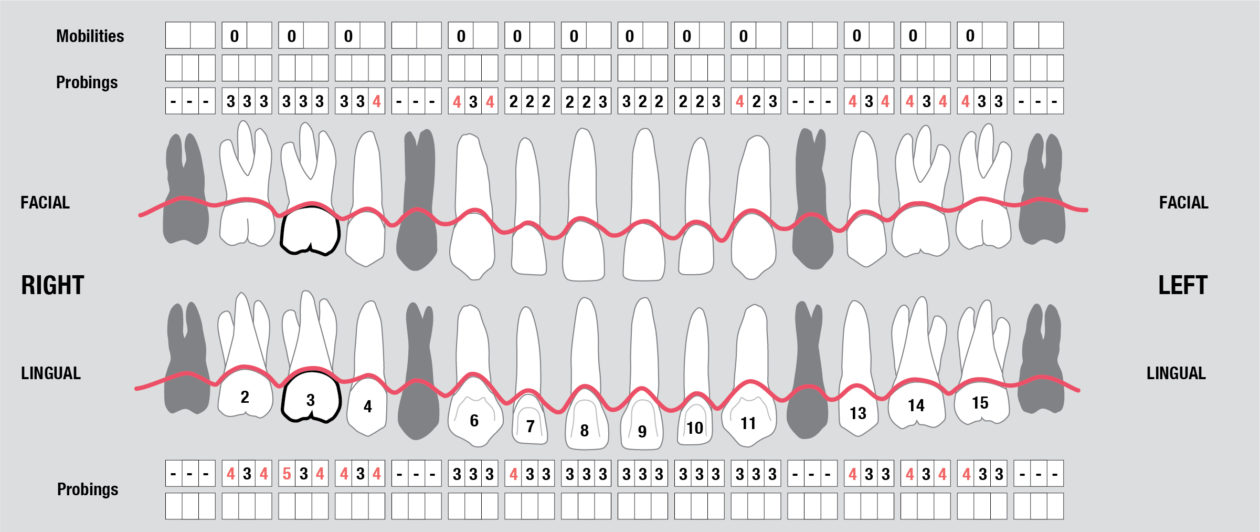

Full Mouth Radiographic Series, Maxillary and Mandibular Intraoral Scans, Digital Jaw Relation Recording with a Leaf Gauge, Complete Photographic Series, Periodontal Charting, Restorative Charting.